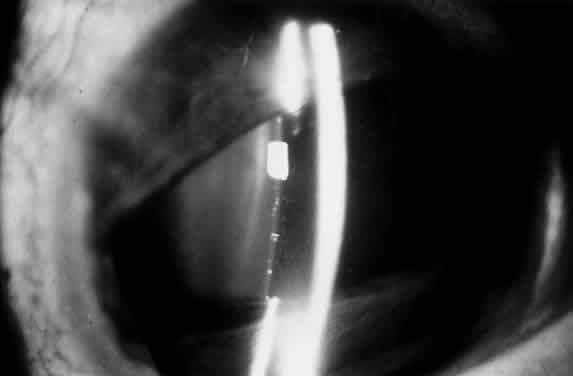

POSTERIOR KERATOCONUS

Posterior keratoconus is a rare corneal disorder characterized by a localized craterlike defect on the posterior corneal surface, with the concavity facing toward the anterior chamber (Fig. 9).111 The anterior corneal surface is normally sculpted. Vision may be normal or slightly reduced. Reduced vision may be secondary to scattering of light from the irregular posterior surface, or to a steepening of the anterior cornea in the region of the posterior defect.112 Posterior keratoconus may be either unilateral or bilateral. It is frequently nonfamilial, although it has been described in a parent and sibling in three families and in siblings in another family.111,113,114

Fig. 9. Posterior keratoconus. A. Direct illumination. B. Slit-lamp image demonstrating the concave defect. (Courtesy of James J. Reidy, MD)

Histopathologically, Descemet's membrane is present but may show thinning, abnormal anterior banding, and posterior excrescences.111,115 The endothelium is intact but displays cytoplasmic vacuolation and attenuation adjacent to the posterior excrescences.111 Several theories have been proposed to explain the pathogenesis of congenital posterior keratoconus. Mann suggested that posterior keratoconus is caused by an arrest of corneal development and the resulting persistence of embryonal characteristics.116 Greene117 explained the origin of posterior keratoconus as the result of delayed separation of the lens from the cornea.